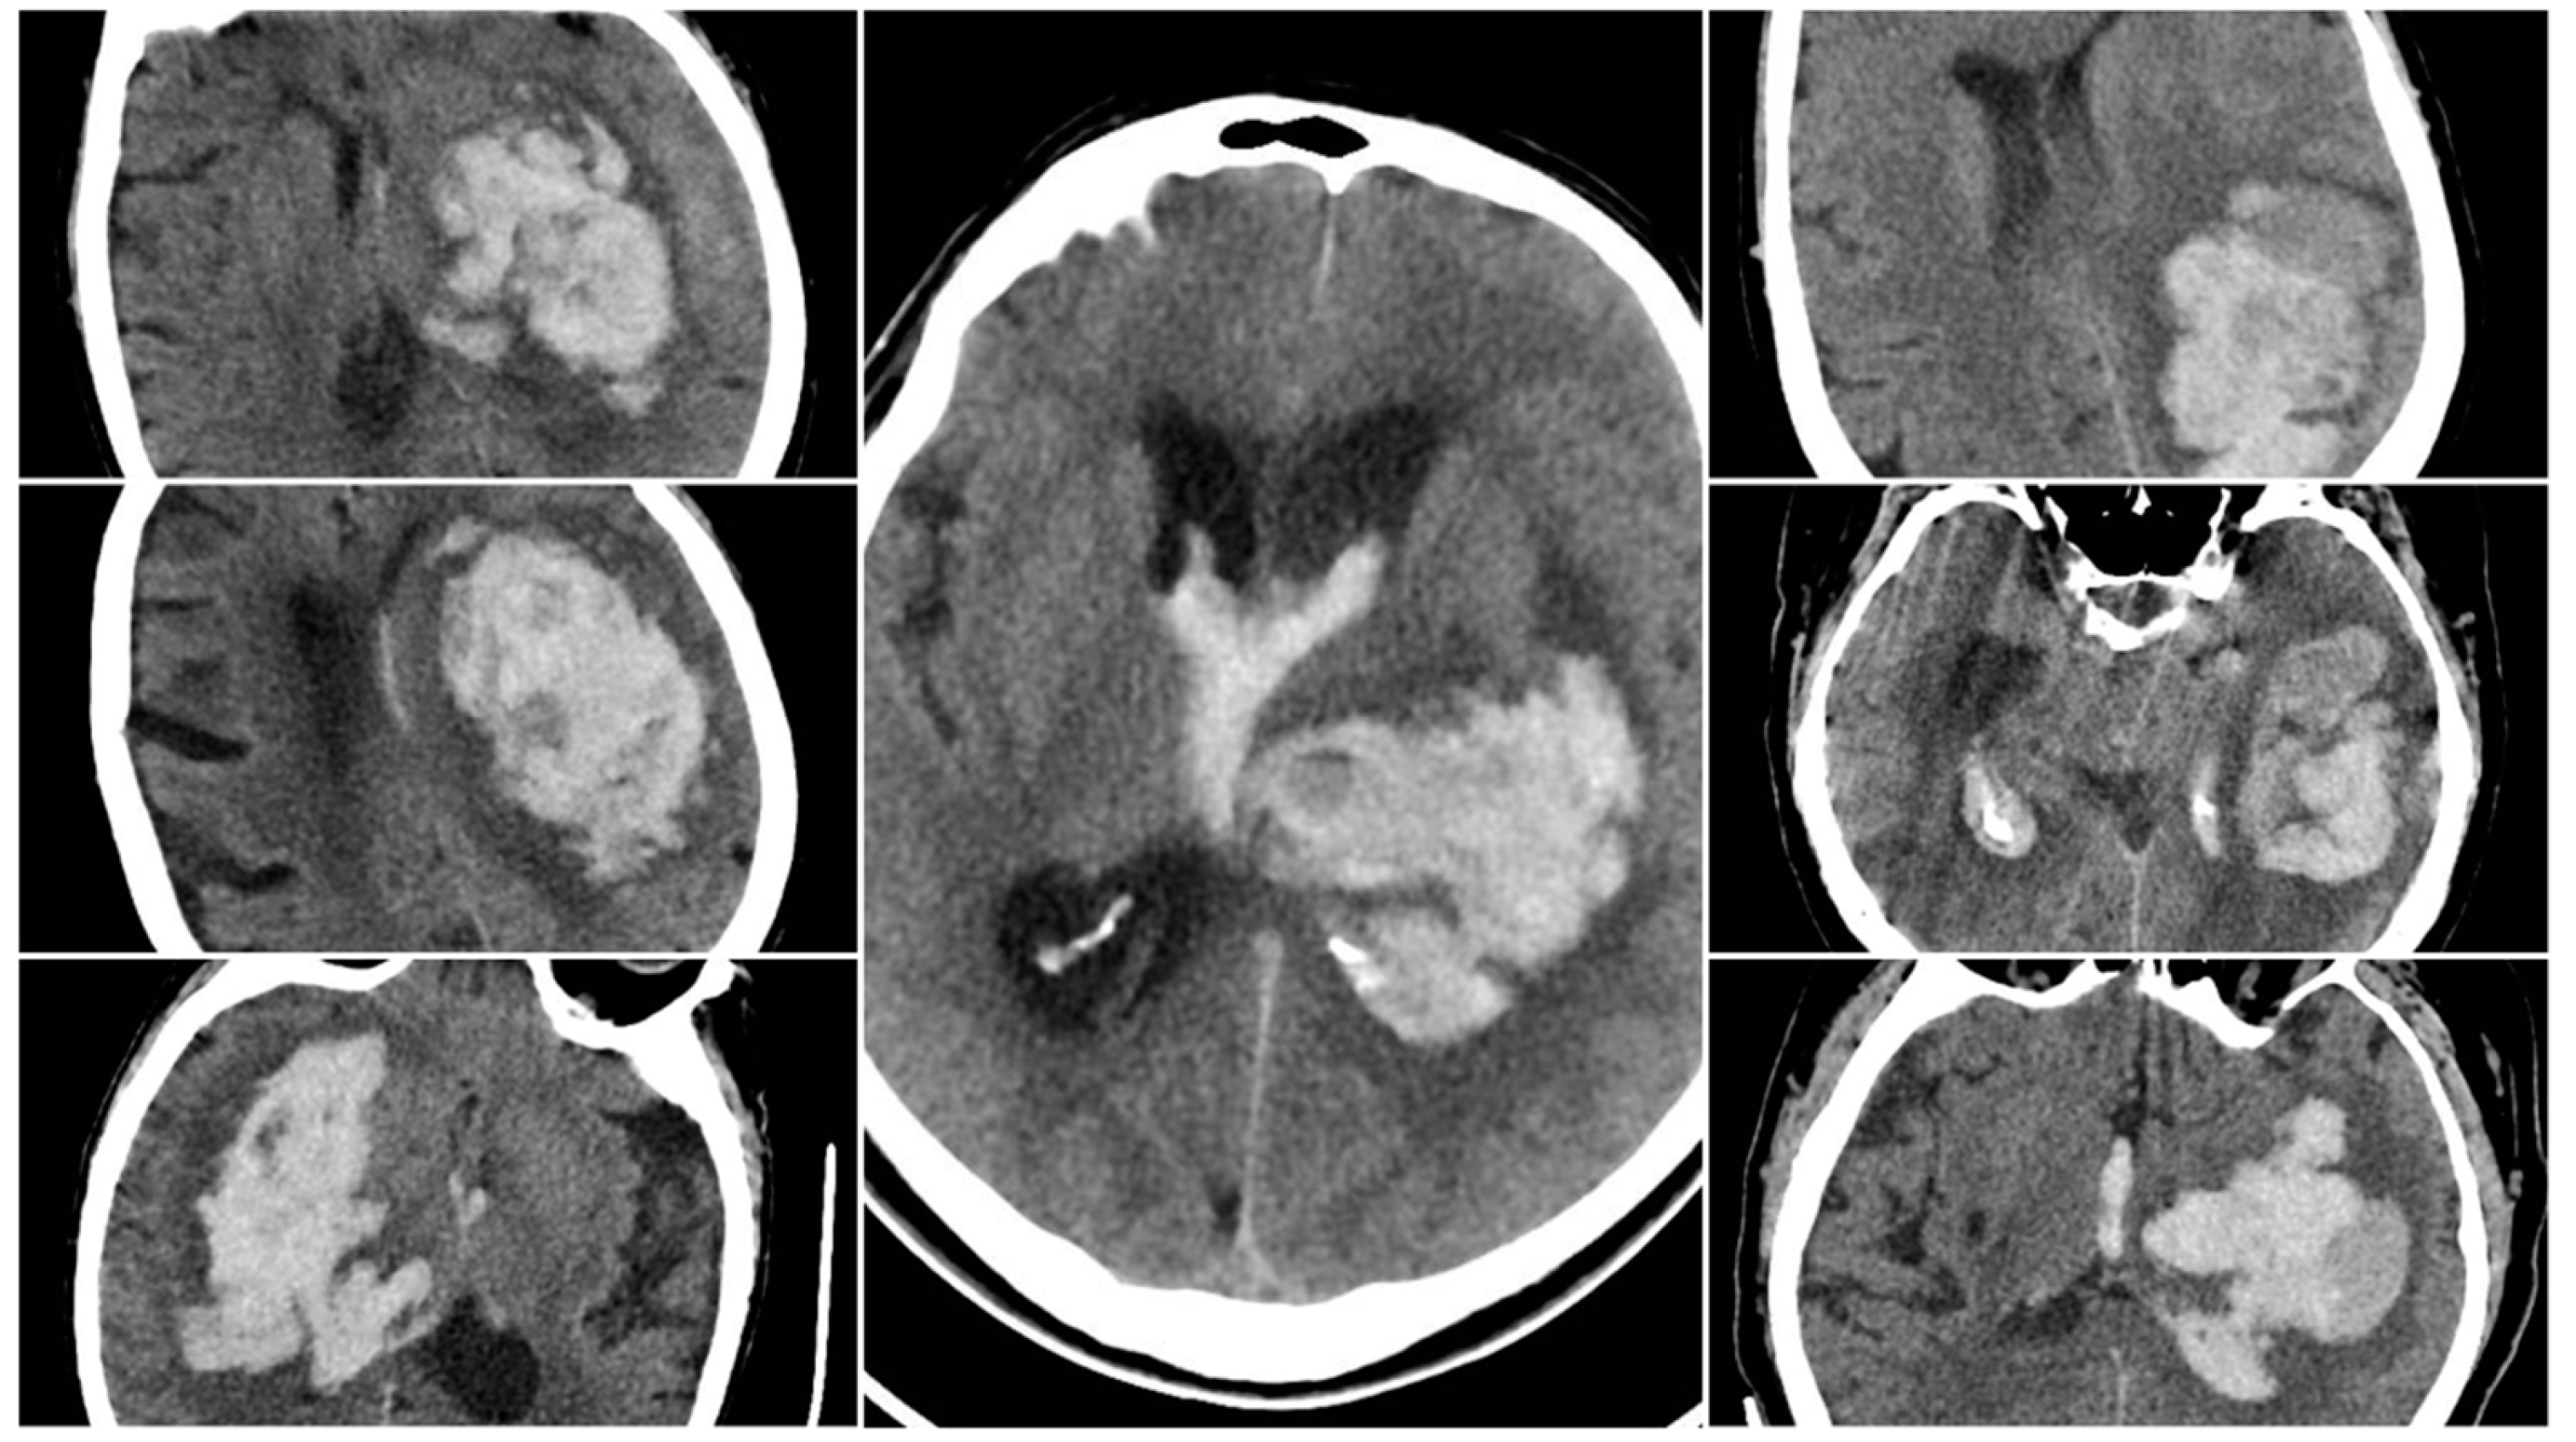

All eligible patients underwent a baseline NCCT scan upon presentation, followed by a second NCCT within 24 hours or sooner if clinical deterioration occurred, to detect hematoma expansion. Four key radiological signs were evaluated on the initial NCCT. The Blend Sign (BS) was recorded when a well-defined hypoattenuating region directly abutted a hyperattenuating area within the same hematoma, differing by ≥18 HU, without the hypodense portion being fully encapsulated by the hyperdense region (BS=1 if present, otherwise 0).

Figure 1. Blend Sign (BS) – three examples from our cohort.